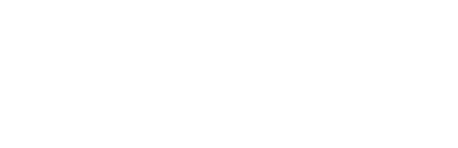

Technical report

A box-shaped, shielding device for reducing the risk of COVID-19 droplet infection during gastrointestinal endoscopic procedures

COVID-19

Endoscopy

Gastroenterology

Infection prevention